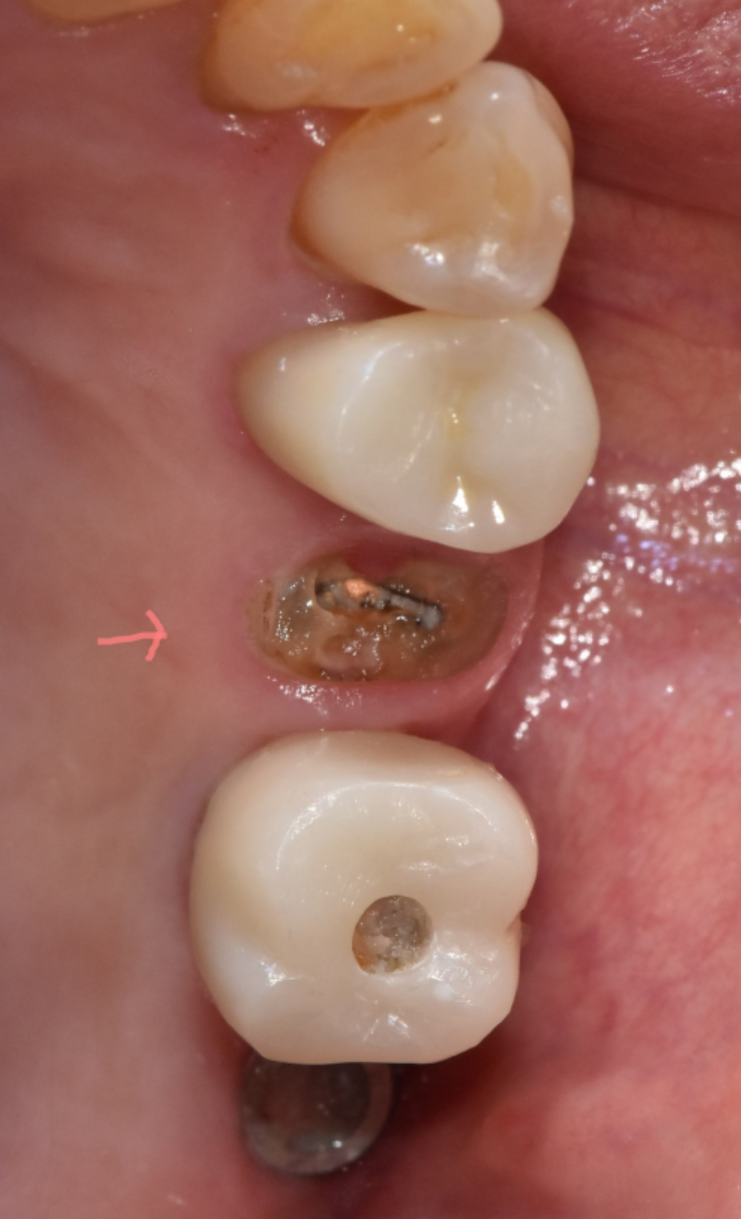

충치가 신경과 뿌리까지 내려가 치아 구조가 무너진 경우

-

치아가 뿌리에서 파절된 경우

크라운을 지탱할 남은 치질이 거의 없는 경우

250724 남아있는 치질이 거의 없는 경우

빠진 크라운을 그대로 다시 붙이면 문제가 해결될 것 같지만,

내부 치아의 상태가 건강하지 않다면 재부착은 임시방편에 불과합니다.